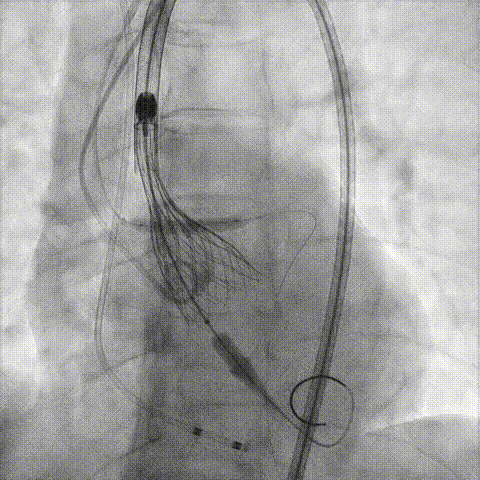

冠脉造影

手术策略和器械选择

预置Telescope™导引延长导管及导丝保护左冠,

18mm球囊预扩张再次评估冠脉闭塞风险。

介入经过及结果

Telescope™+Runthrough

18mm*40mm 预扩张

预埋 Resolute Integrity 3.5*26mm

再次评估左冠开口

第一次释放

再次评估左冠开口,考虑调整瓣膜深度

回收后调整深度,再次释放

评估左冠开口

左冠开口切线位造影

决定左冠烟囱支架保护冠脉

调整支架位置

释放冠脉支架

释放瓣膜

造影评估

支架内后扩张

根部造影

最终结果